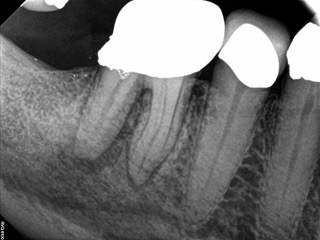

A body of research has emerged in recent years on the management of severe dental pain, exemplified by the diagnosis of an acute apical abscess where drainage cannot be achieved, symptomatic apical periodontitis, or irreversible pulpitis.11 An example of an acute apical abscess is depicted in Figure 1 and Figure 2. These conditions typically represent the most severe discomfort experienced by patients, and consequently, they serve as an excellent model for pain management. Treatment strategies for these issues and other painful conditions should include both definitive treatments for the diagnosed condition as well as adjunctive pharmacologic management.

(1.) A 74-year-old male presented with an acute apical abscess associated with tooth No. 30. The pre-operative periapical x-ray revealed evidence of apical pathology.

Figure 1